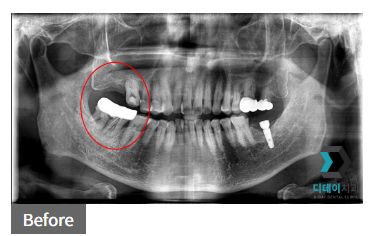

231115

240207